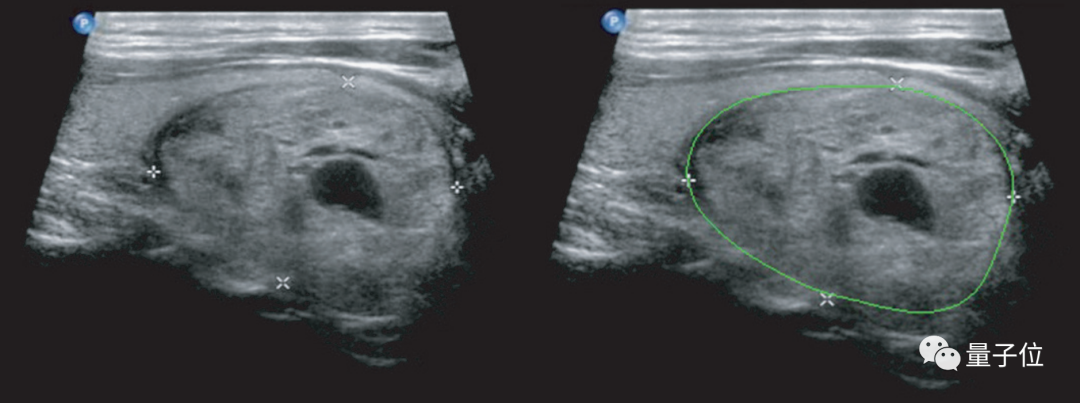

△ 使用深度学习进行的甲状腺结节检测和定性诊断(右)

这种AI辅助诊断的准确度,当时就已经比中国甲等医院的放射科医生至少高出10%。

当然,这并不是说医学影像AI应用会取代医生,而是让影像科医生在辅助下能有更高的工作效率,也可以让经验丰富的医生专注于更复杂的病例。